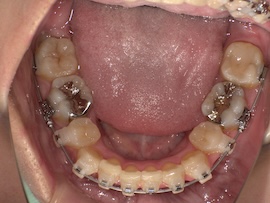

さらに1ヶ月後、

左上の7番目を抜歯してから約9ヶ月が経過しましたが、代わりに活かしていきたい親知らずが出てこないのでついに牽引(歯茎を切って引っ張り出す)をすることになりました。